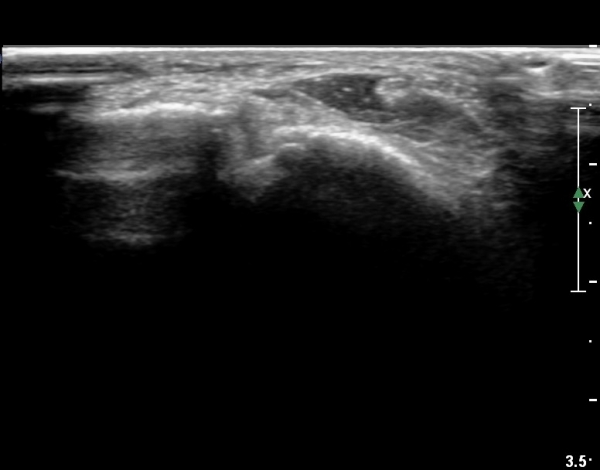

Á¾°ñºñ°ñÀδë Á¾´Ü¸é°Ë»ç¿¡¼­ ÀδëÀÇ ºñ°ñºÎÂøºÎ Àú¿¡ÄÚ ºÎÁ¾°ú ºñ°ñÀÇ °ß¿­°ñÀýÀÌ °üÂûµÈ´Ù(»çÁø 5, 6, 7).

Á¾°ñºñ°ñÀÎ´ë ºÎÇϰ˻翡¼­ Á¾°ñÀÇ °úµµÇÑ ¿òÁ÷ÀÓÀÌ °üÂûµÈ´Ù(÷ºÎµ¿¿µ»ó 3, 4).

ºÎÇÏ°Ë»ç °á°ú·Î º¼ ¶§ ÀδëÀÇ ºÎºÐÆÄ¿­·Î ÆÇ´ÜµÈ´Ù.